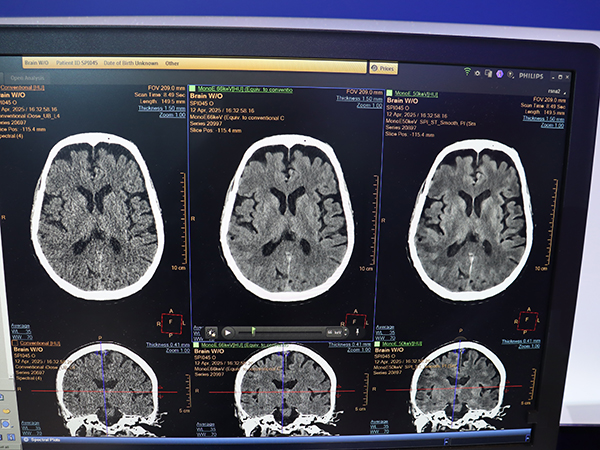

MRIでは,世界初の3.0TヘリウムフリーMRI「BlueSeal Horizon」(510 k Pending,薬機法未承認)が登場。一方,CTはスペクトラルCT「Verida」(510 k Pending,薬機法未承認)が発表された。Veridaに搭載される第3世代の二層検出器はAI画像再構成に最適化しており,AI画像再構成「Spectral Precise Image」により高解像度なスペクトラル画像を全身領域で取得できる。

AI画像再構成「Spectral Precise Image」と仮想単色X線画像(MonoE)により解像度とコントラストが向上(右)